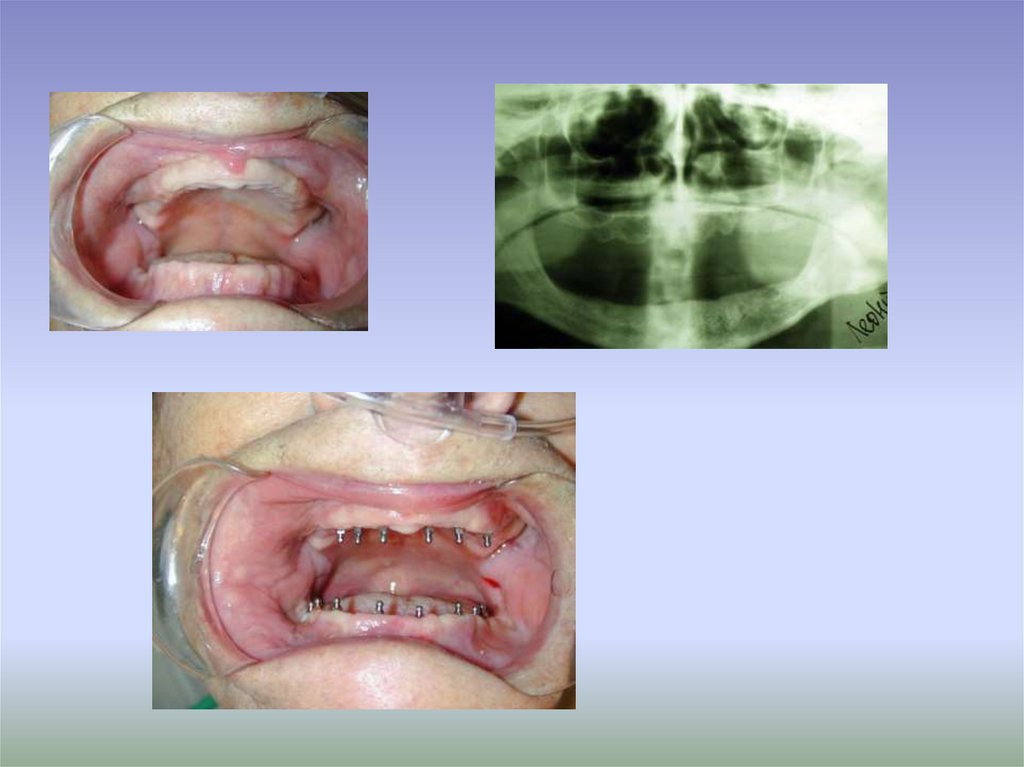

16. Мини-импланты